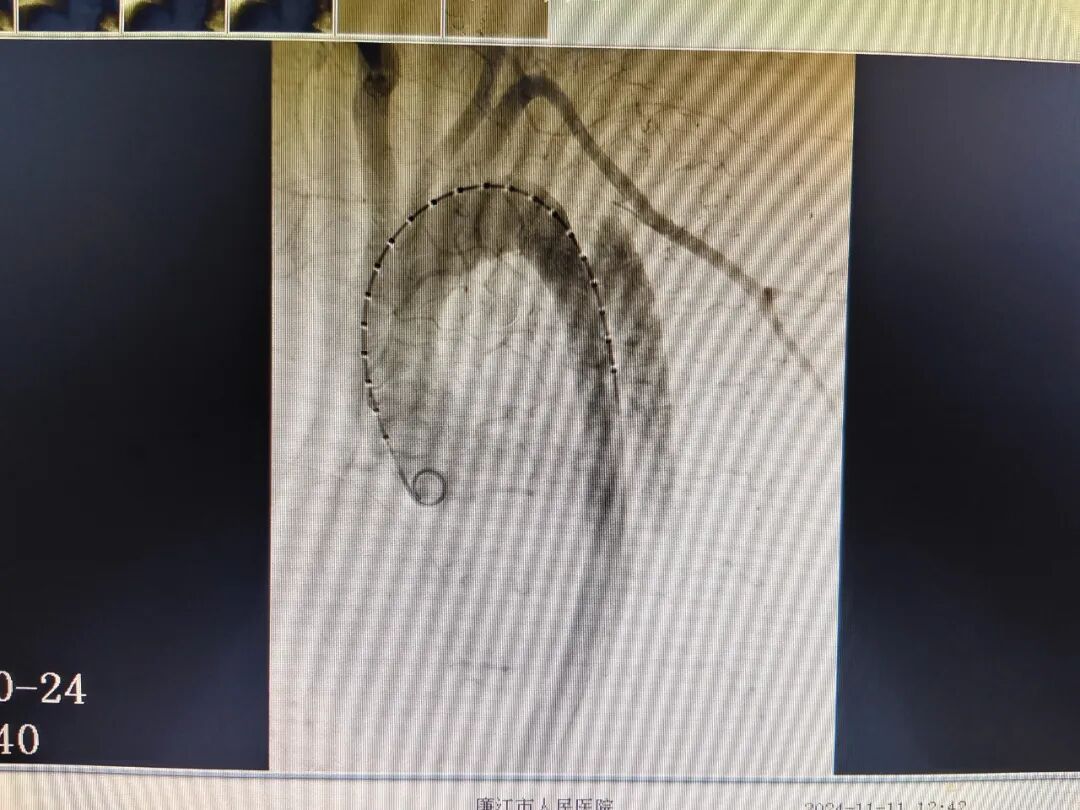

近日,廉江市人民医院心血管内科团队成功完成首例主动脉造影+胸主动脉覆膜支架腔内隔绝术,标志着廉江市人民医院在胸主动脉疾病的救治领域取得了新突破,介入治疗技术水平再上新台阶。

据了解,患者李某为45岁男性,因“胸痛3小时”入院,既往有高血压病3级,脑出血遗留左侧肢体偏瘫病史,平素不规律服药治疗。急诊检查心电图未见心肌梗死改变,结合患者心电图、胸痛症状,考虑可能是主动脉夹层,为患者行急诊主动脉CTA检查,确诊为:1.胸、腹部主动脉夹层(Debakey Ⅲ型);2.高血压病3级(很高危组)。该患者病情危急,随时有主动脉夹层破裂的风险,一旦破裂,将会危及患者生命。医院迅速组织多学科会诊,讨论分析、评估病情后,制定详细的手术治疗方案。完善术前准备,心血管内科团队为患者行气管插管全麻下主动脉造影+胸主动脉覆膜支架腔内隔绝术。术后予重症监护,维持内环境稳定等积极治疗后,患者已情况好转出院。

术前

术后